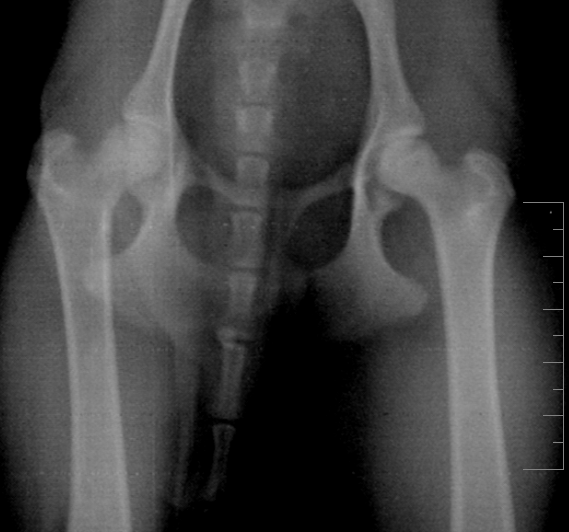

Обнаружено при осмотре: объём движений в правом ТБС ограничен, мышечный корсет атрофичен. При проводке хромота опирающейся конечности. При максимальных отведениях назад правого ТБС острая боль.

Заключение: перелом по вертлужной впадине правого ТБС

Вот теперь более-менее понятна картина. По перечисленным симптомам очень похоже на болезнь Пертеса, или остеохондропатию головки бедренной кости. На снимке явно заметна деформация головки правого сустава, левый в порядке: круглый, ровный, гладкий. Трещины на правом не видно, поэтому я бы не стала исключать другой диагноз. Врачу, конечно, виднее, но снимки можно показать и другому специалисту и выслушать его мнение. Пертес часто ошибочно связывают с травматикой, в то время как заболевание имеет наследственный характер и чаще ему подвержены мелкие породы собак. Подробнее - в интернете, а мне больше нечего добавить. Надеюсь, собачка получит своевременную помощь и лечение.

на всякий случай приложу ещё два увеличения

на всех снимках слева - правая нога

Lika-MV, к сожалению, Вы оказались абсолютно правы: это болезнь Пертеса. Причём, врач предположил это сам, после осмотра, ещё до того, как сделал снимки, несмотря на то, что заключение центровета было "трещина".

Снимков делали два, но второй снимок аж три раза: всё время Скобелева качество не удовлетворяло. Диагноз подтвердился: "асептический аваскулярный некроз головки правой бедренной кости"